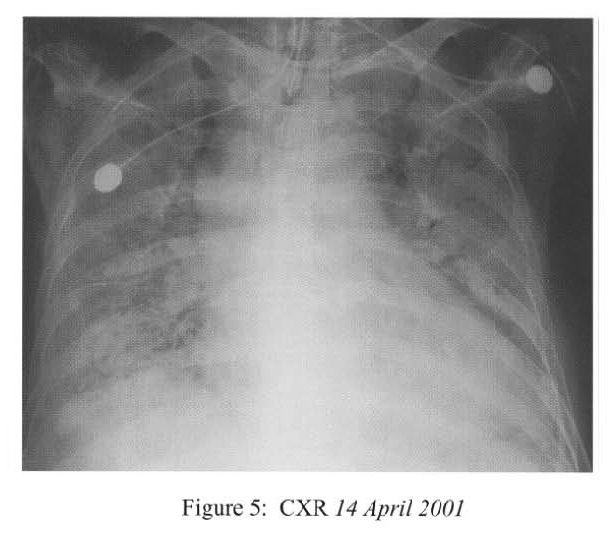

She developed swinging fever in the next few days and Vancomycin was added. However her general state continued to deteriorate with rapid radiological progression to adult respiratory distress syndrome (Figure 5), and cardiovascular collapse. She died 28 days after hospital admission.

Radiological features are also diverse and variable 15,16.On the chest radiograph, early signs include miliary shadows, diffuse reticular interstitial opacities, patchy alveolar opacities, segmental or lobar opacities. In the advanced stage, there can be extensive airspace shadows affecting both lungs, with occasional pleural or pericardial effusion. Without treatment, ARDS quickly evolves. Rarely, ARDS develops after antihelminthic treatment due to release of toxic breakdown products 17.On the abdominal radiograph, there can be thickened mucosal folds, segmental small bowel dilatation or perforation. Among all these variable radiological features, a characteristic pattern of Strongyloides hyperinfection has been described by the radiologists of Hong Kong, which consist of fleeting and rapidly changing CXR signs, predominant small bowel abnormality on AXR, and close temporal relationship of CXR & AXR signsl8. Detection of larvae in stool or other specimens is difficult (Table 1). Serological diagnosis19 is an attractive alternative but it is not available in Hong Kong.

Radiological features are also diverse and variable 15,16.On the chest radiograph, early signs include miliary shadows, diffuse reticular interstitial opacities, patchy alveolar opacities, segmental or lobar opacities. In the advanced stage, there can be extensive airspace shadows affecting both lungs, with occasional pleural or pericardial effusion. Without treatment, ARDS quickly evolves. Rarely, ARDS develops after antihelminthic treatment due to release of toxic breakdown products 17.On the abdominal radiograph, there can be thickened mucosal folds, segmental small bowel dilatation or perforation. Among all these variable radiological features, a characteristic pattern of Strongyloides hyperinfection has been described by the radiologists of Hong Kong, which consist of fleeting and rapidly changing CXR signs, predominant small bowel abnormality on AXR, and close temporal relationship of CXR & AXR signsl8. Detection of larvae in stool or other specimens is difficult (Table 1). Serological diagnosis19 is an attractive alternative but it is not available in Hong Kong.